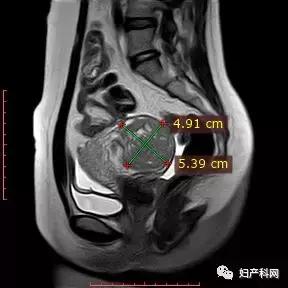

2018年10月就诊时MRI